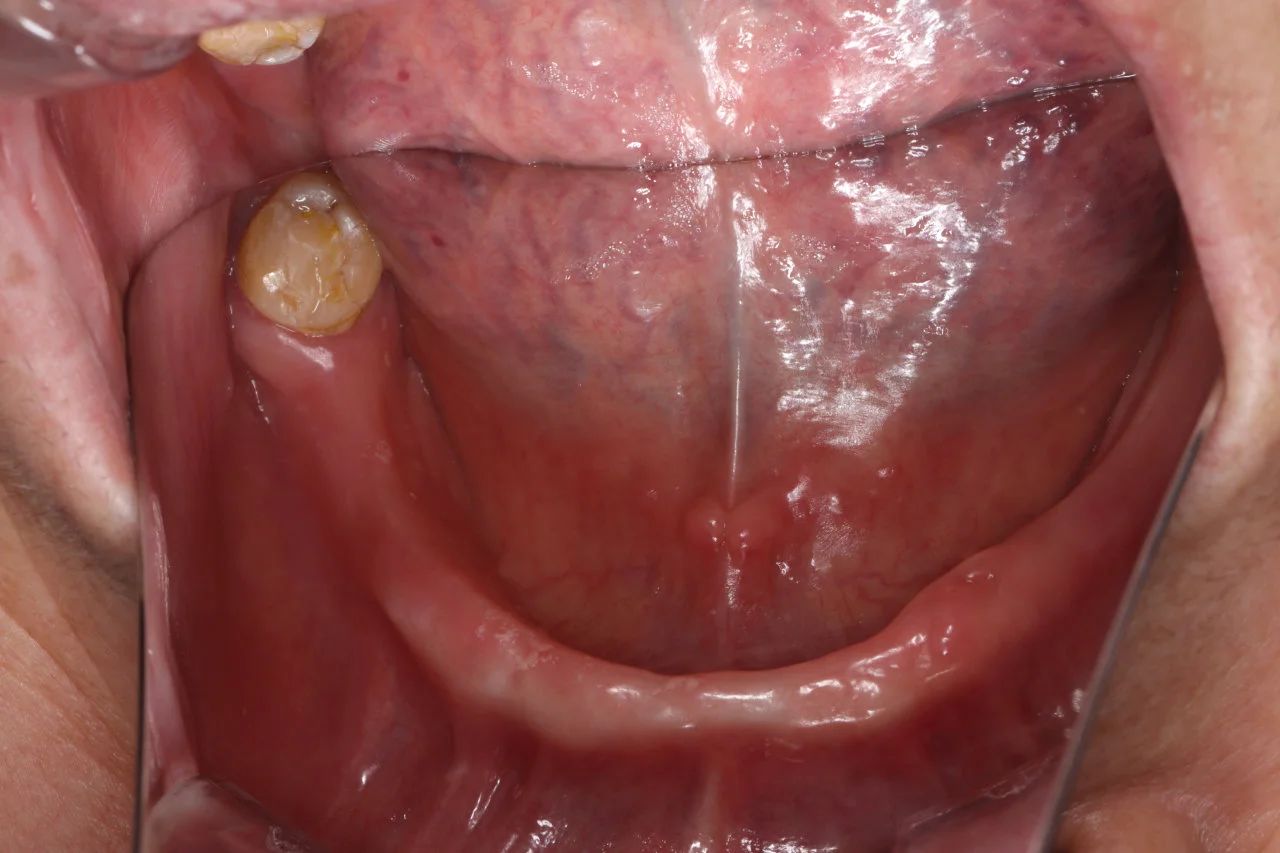

-下半口种植+即刻修复前-

-下半口种植+即刻修复前-